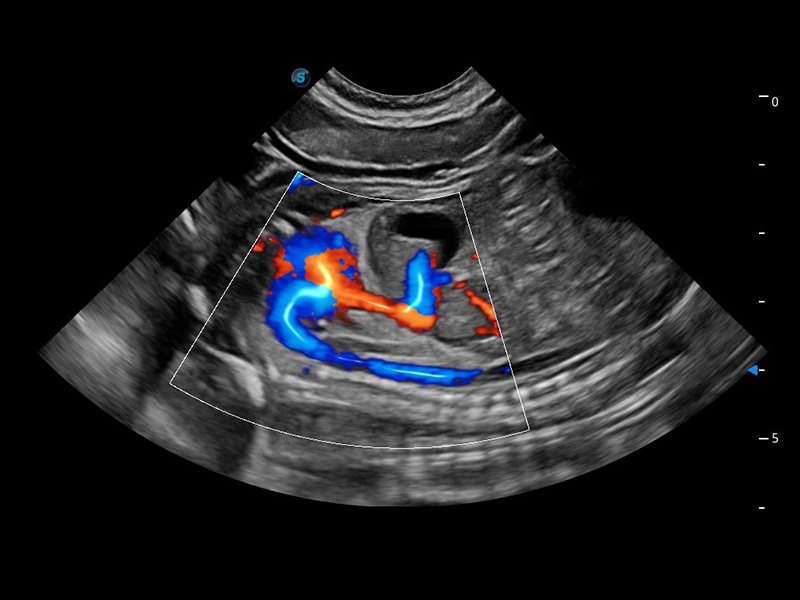

(猫)髂动脉血流频谱